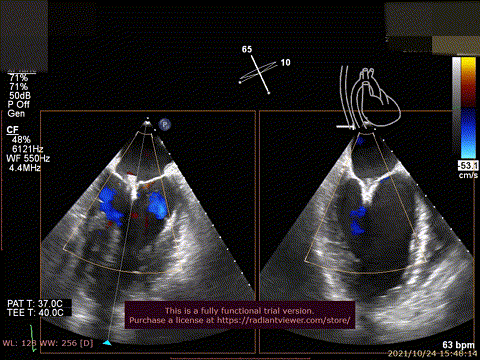

62岁老年男性,诊断为重度二尖瓣反流,病程长,经过反复治疗,调整药物,仍具有明确临床症状,心功III-IV级,经胸超声心动图提示二尖瓣功能性反流4+,左心射血分数35%,左心室舒张末期内径71mm,反流位于A2/P2,累及范围较广(视频1),患者合并严重慢性阻塞性肺部疾病,支气管扩张,肺动脉收缩压增高,甲状腺功能异常。